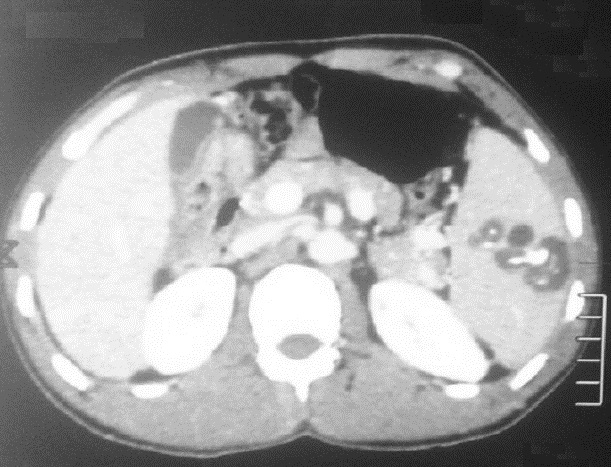

Image radiologique TDM + contrast

intraveineuyse d'un kyste hydatique multiple de la

rate . Aspect radiologique TDM est des kystes

ovalaire hy podensite a bord fine et nette , lisse

situe dans la parenchyme de la rate en forme de

rosette avec de vesicule de fille endocavitaire .

C'est la kyste hydatide de type 2 actif ( CE2) selon

la classification 2001 de OMS |

|

Même cas en coupe coronale .

Les kyste sur cette coupe etre en vue très nette et

n,a pas de rehausse apres injection de contrast

intraveineuse . Image radiologique TDM plus + C+ en

coupe coronal . L'exament serologique specifique d'

echynoccocus se verifier la diagnoctic |